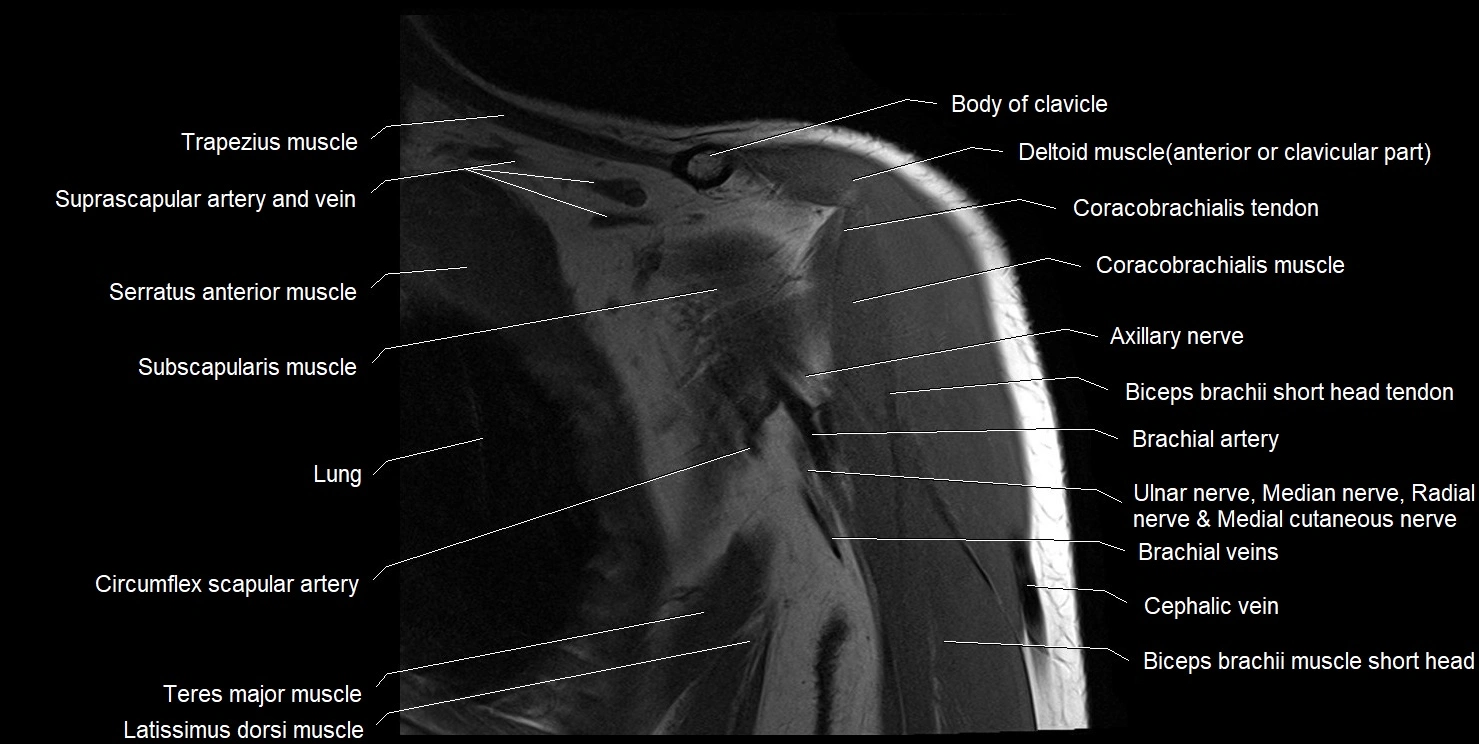

CT image

image